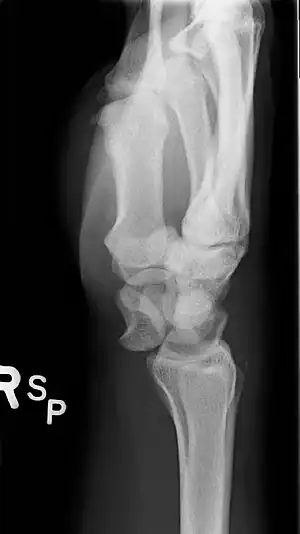

A lateral X-ray of the wrist showing a lunate dislocation